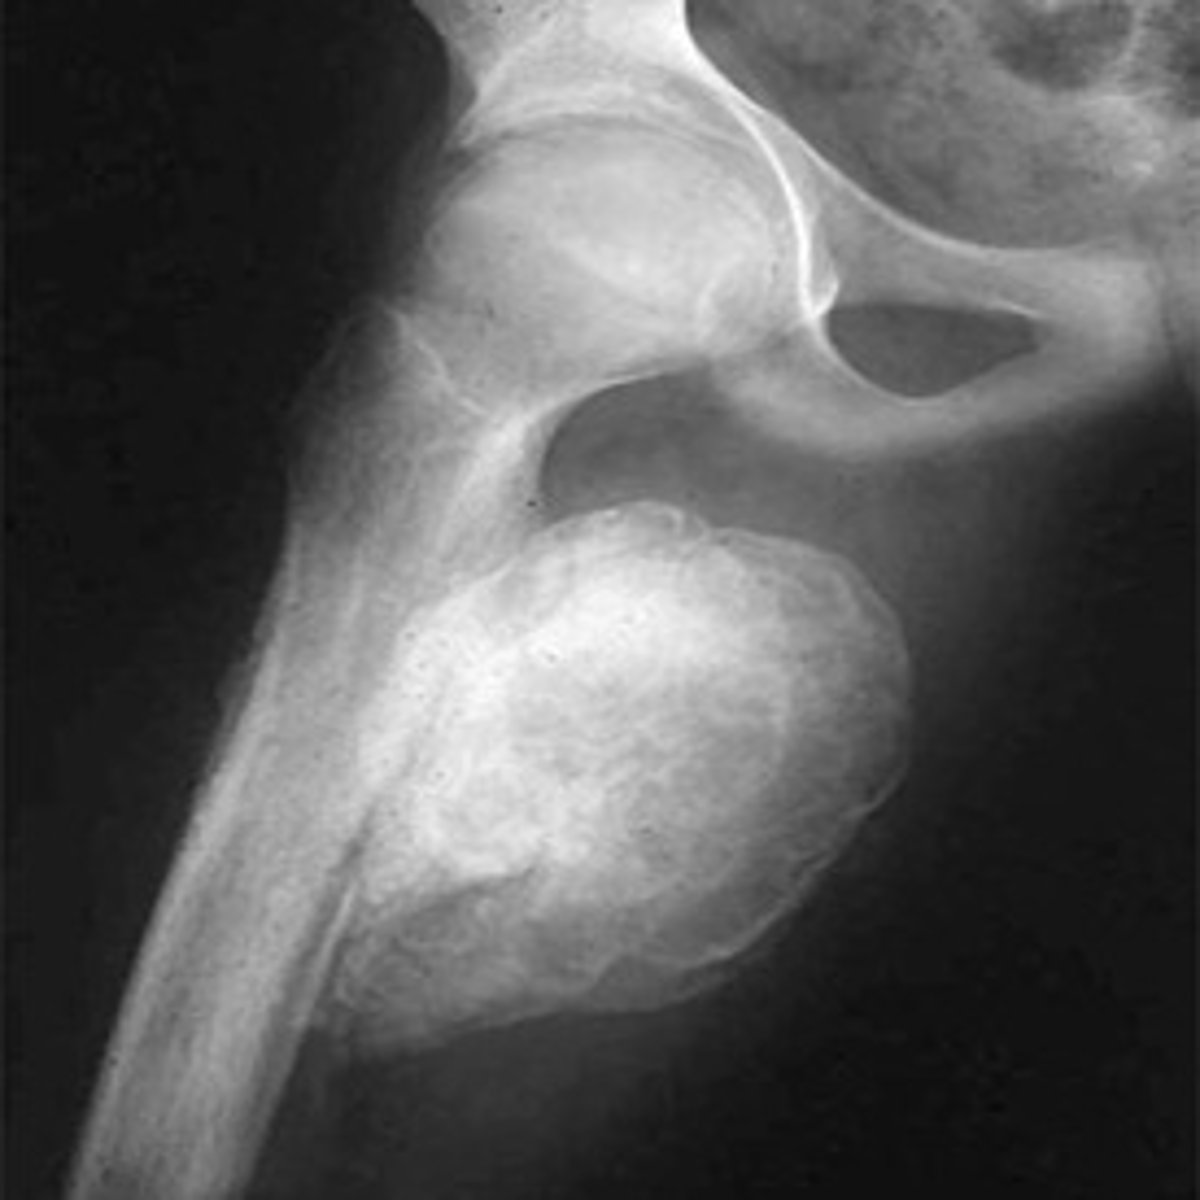

myositis ossificans

-common in brachialis muscle as result of trauma, aggressive stretching